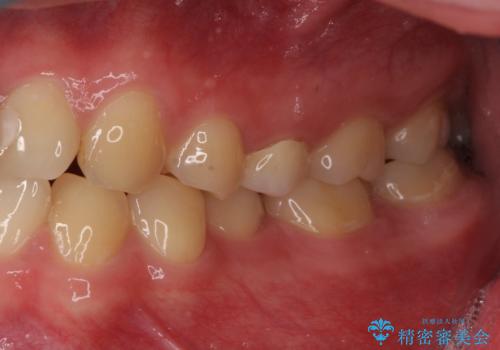

- 「左右どちらとも、どこかが痛む」とご来院された患者様です。

他院で虫歯治療を複数行っており、原因となりうる歯がいくつかありました。まずレントゲン上最もあやしい右上から治療開始しました。右上の歯は1本割れていたため、部分矯正で引っ張り出しました。

右上もう1本と左上は虫歯治療(セラミックインレー、セラミッククラウン)を行いました。

他院で虫歯治療を複数行っており、原因となりうる歯がいくつかありました。まずレントゲン上最もあやしい右上から治療開始しました。

右上の被せものを除去したところ、中で歯が割れていたため、部分矯正で引っ張り出すことになりました。